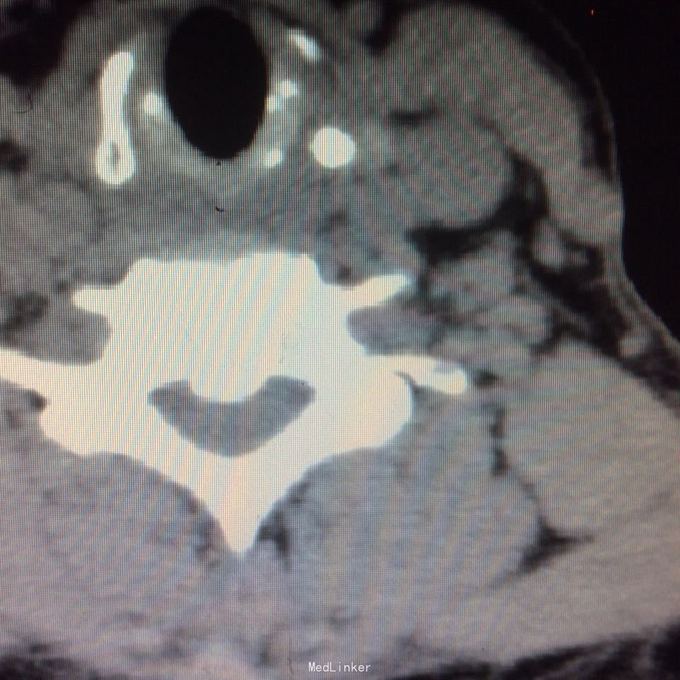

压头及右侧臂丛牵拉试验阳性,无明显浅感觉减退,右上肢肱三头肌肌力2级,双上肢腱反射活跃,双上肢病理征阳性 颈椎ct见颈椎6、7水平后纵韧带骨化,继发相应的椎管水平狭窄,自带核磁见颈椎2-7间盘向后突出,硬膜囊前缘受压